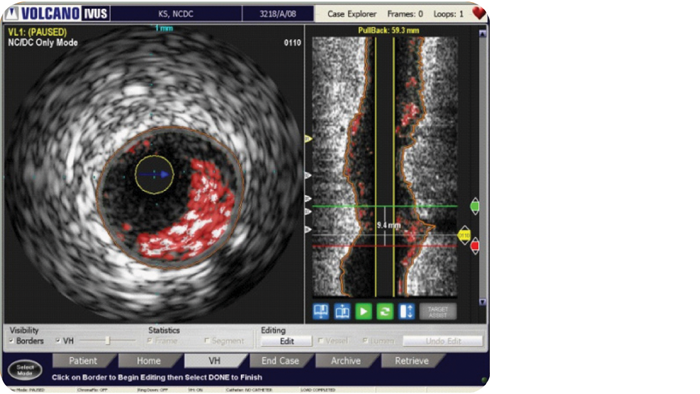

VH IVUS imaging provides a colorized tissue map of plaque composition with automated lumen and vessel measurements.* VH IVUS technology uses advanced, proprietary spectral analysis techniques to classify plaque into four tissue types with 93-97% accuracy.1

For complete lesion assessment, VH IVUS provides a colorized tissue map of four tissue types:

VH IVUS provides automatic border contours for full segment analysis.